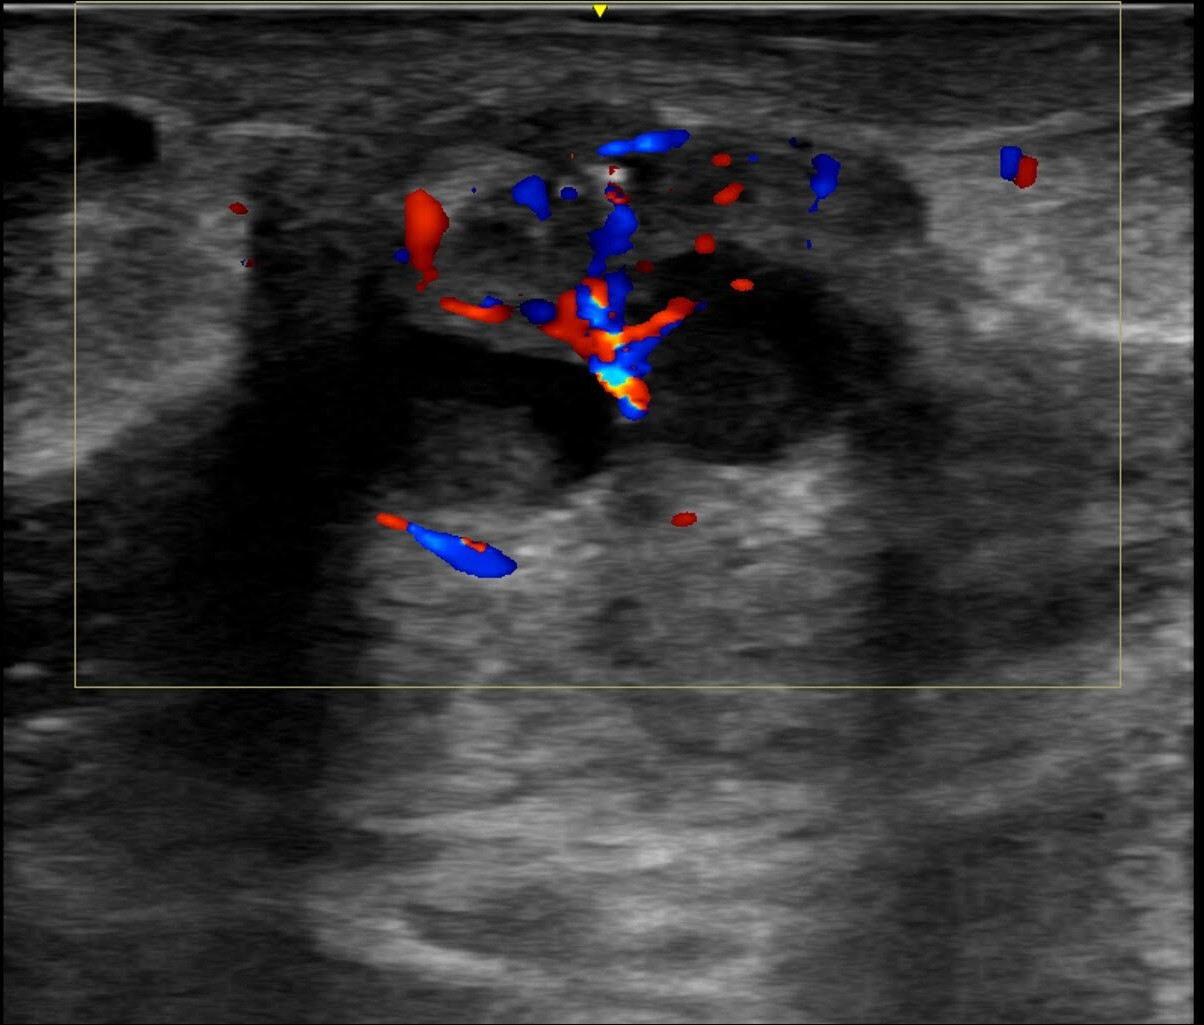

Figura 2. En el estudio Doppler se identifica un aumento de la vascularización de los tejidos circundantes.